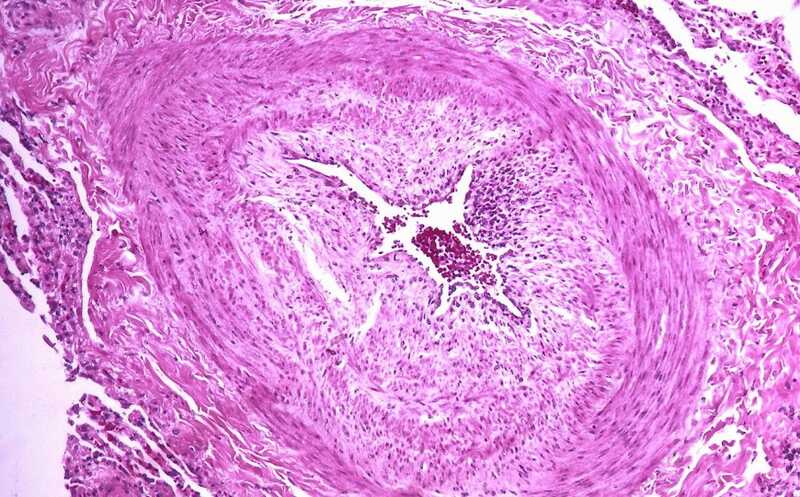

Артериальная легочная гипертензия — опасное заболевание, при котором повышается кровяное давление в легочных артериях и артериолах, что со временем приводит к отказу правого желудочка и смерти. При этом состоянии происходит ремоделирование кровеносных сосудов легких, вызванное усилением пролиферации и подавлением апоптоза эндотелиальных и гладкомышечных клеток. Несмотря на прогресс в методах лечения, множество пациентов все еще умирает от легочной гипертензии или испытывает существенные ограничения в физических нагрузках. Сотатерцепт — препарат для подкожного введения, содержащий рекомбинантный белок на основе фрагмента рецептора активина второго типа и кристаллизующегося фрагмента иммуноглобулина Fc (ACTRIIA-Fc) — стабилизирует процессы патологического ремоделирования легочных сосудов, ингибируя активиновый сигналинг. Препарат, который продается, в частности, под торговым наименованием Винревэйр (Merck Sharp and Dohme), уже продемонстрировал эффективность на пациентах с длительной (в среднем 8 лет) гипертензией.